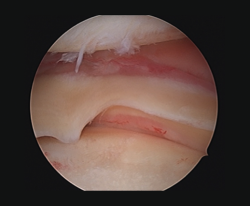

Meniscal ramp lesions

Although recently greater importance is being placed on the presence of so-called meniscal ramp lesions (Figure 3), with an estimated incidence of up to 23.9%(19) associated to ACL rupture, these lesions were already described by Strobel(20) in 1988 as a particular type of meniscal injury associated to ACL rupture and affecting the peripheral insertion of the posterior horn of the medial meniscus. These injuries are also referred to as hidden lesions of the posterior horn of the medial meniscus, since they may go undetected in the MRI studies(21). From the biomechanical perspective, ramp lesions of the knee with ACL rupture increase anterior translation of the tibia, internal and external rotation, and pivot shift. If not repaired, rotational stability following reconstruction of the ligament likewise is not fully restored(22).

[[{"fid":"4712","view_mode":"default","fields":{"format":"default","alignment":""},"type":"media","field_deltas":{"3":{"format":"default","alignment":""}},"link_text":null,"attributes":{"class":"media-element file-default","data-delta":"3"}}]]

Diagnosis

No clinical test is currently available allowing us to suspect the presence of these lesions. Magnetic resonance imaging is the diagnostic technique of choice, with the description of two signs associated to this disorder: the presence of an irregularity at the posterior margin of the medial meniscus, and the presence of joint fluid in the space between the posterior horn and the capsule(21). It has also been shown that the presence of edema in the posterior zone of the medial tibial plateau increases the probability of a meniscal ramp lesion(23). The definitive diagnosis is based on the arthroscopy findings. Authors such as Sonnery-Cottet(24) have described a systematic surgical exploration protocol to prevent such lesions from going undetected. In this exploration they recommend the use of a posteromedial port in order to allow improved visualization and even use a palpator probe to test the presence of these lesions, which are sometimes covered by a kind of membrane.